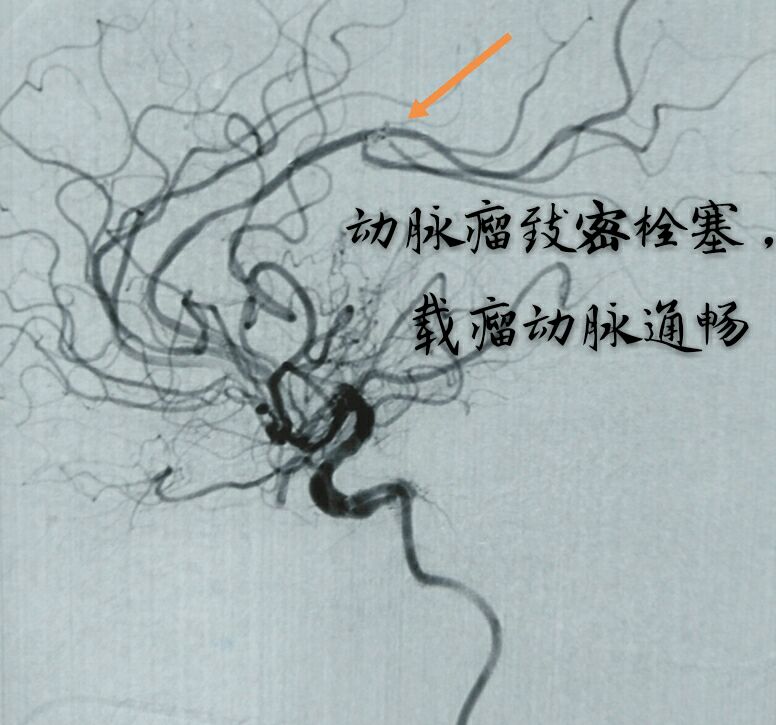

病例十二:中年男性患者,右侧大脑中动脉分叉部动脉瘤,宽颈,形态不规则,瘤颈部分支众多

因瘤颈下方分支与动脉瘤关系密切,角度刁钻,而血管纤细,无法用辅助支架保护,术前做了详细、精准的计划,决定用双微导管技术栓塞

双微导管交替成栏栓塞,利用弹簧圈之间互相缠绕稳定弹簧圈